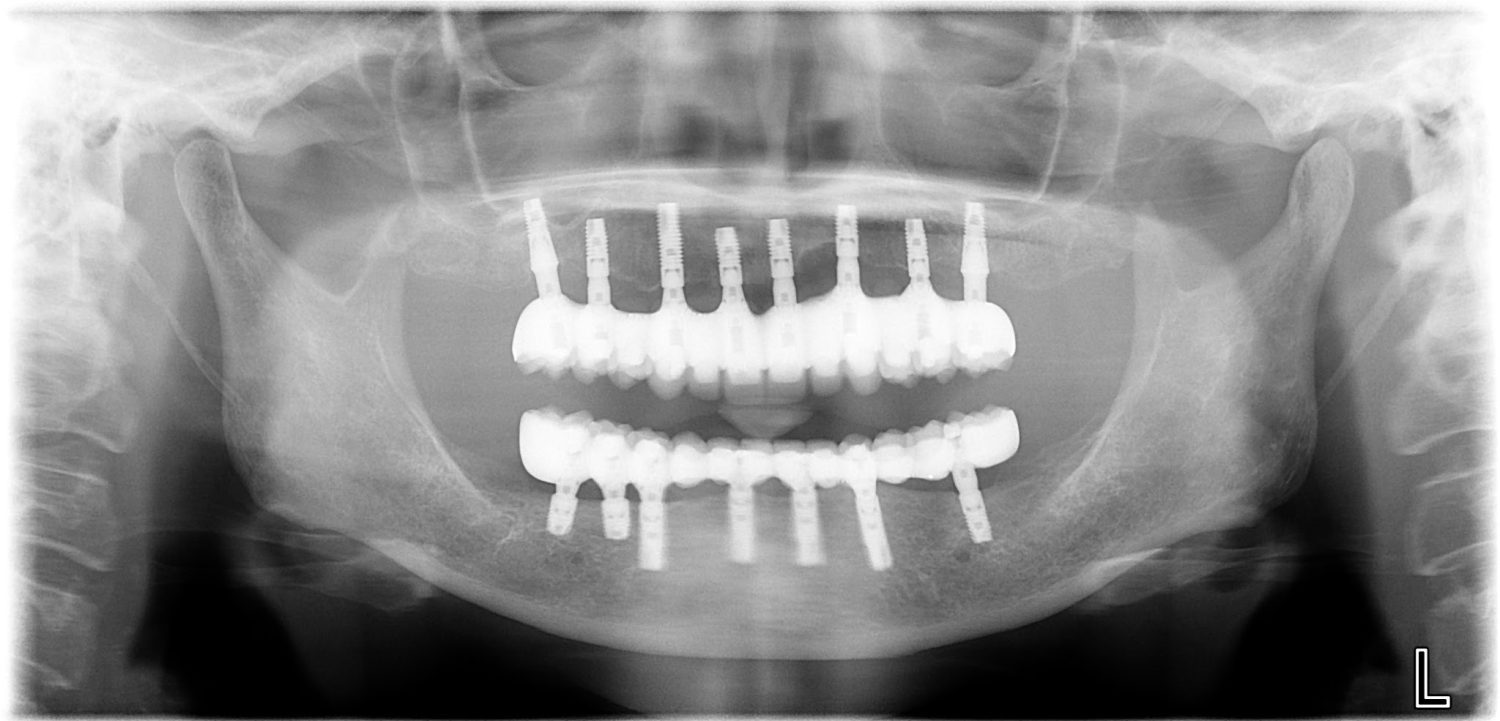

インプラント治療の症例紹介⑤

Before

After

主訴

歯肉腫脹、咬めるようにしたい

治療内容

重度歯周病により全ての残存歯保存不可能な状態。上下顎ボーンアンカードブリッジによる咬合再構成。

治療費

12,621,400円(税込)

治療期間

22ヶ月

通院回数

28回

想定されたリスク

※上部構造の形態が複雑になるため清掃が難しくなる、インプラント周囲炎の恐れがありました。

濱 仁隆先生

浜歯科

上顎8本下顎7本のインプラント体埋入によるボーンアンカードブリッジ。